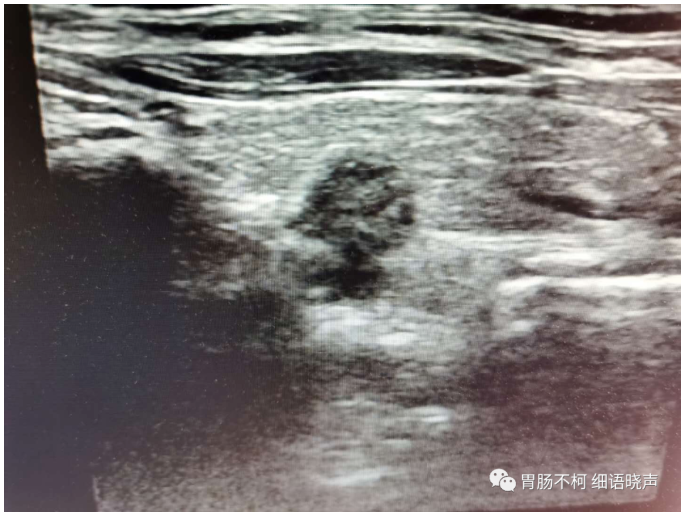

病例五:甲状腺左叶后方凸入甲状腺的低回声结节,纵横比>1,首诊考虑甲状腺癌。

隔日复查,结节的内部回声发生了变化,呈典型混合回声型咽食管Killian-Jamieson憩室的表现。